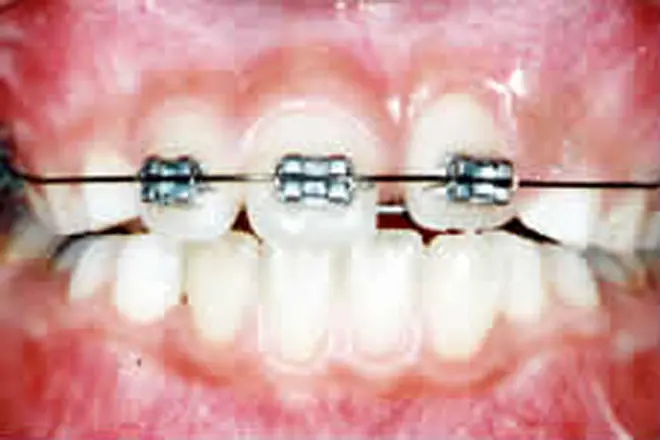

子どもの矯正 治療例4

奥歯が噛み合った状態でも、前歯に隙間ができています。

乳歯が多数あると全体矯正ができないので、歯の裏側に舌突出防止装置を付けました。これにより、舌が前に出る圧力を押さえました。

噛み合わせが整い、デコボコも解消されました。

| 患者さまの年齢・性別 | 13歳・女性 |

|---|---|

| 治療期間 | 2年 |

| 治療費(税込) | 946,000円 |

| 主訴 | 前歯が噛まない |

| 診断名・主な症状 | 開咬 |

| 治療に用いた主な装置 | 舌突出防止装置・表側矯正装置 |

| 治療内容 | 歯の裏側に舌突出防止装置を付け、治療と同時に舌癖を改善するトレーニングを実施しました。 |

| 抜歯部位 | 非抜歯 |